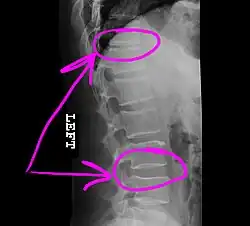

Today, the telestrator is used in a wide variety of applications (from educational, boardroom, church and military presentations to telemedicine conferences), where it can be used by both the near and far ends to annotate precise details of microscopic images or other medical images that are under consultation. The telestrator is also used in courtrooms to communicate details of multimedia images presented to a jury.[2]